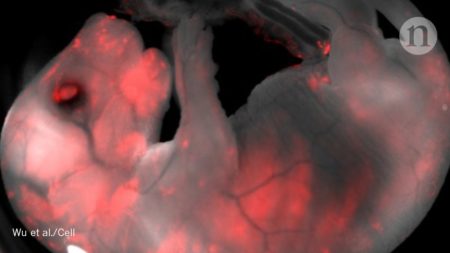

Un equipo internacional de científicos asegura haber creado una ‘quimera’ entre un ser humano y un cerdo gracias a un experimento que ha sido publicado en la revista Cell.

Según la publicación, los científicos introdujeron células madre humanas en embriones de un cerdo en una fase temprana del desarrollo, lo que permitió a los expertos crear unos 2 mil híbridos que luego introdujeron en el organismo de una cerda durante 28 días. Ese período se corresponde al primer trimestre del embarazo de las cerdas, después de lo cual extrajeron el feto, poniendo así fin al proceso.

Los científicos esperan que estos experimentos en el ámbito de la hibridación abran ventanas a la investigación de métodos para crear órganos para trasplantes producidos por las células del propio receptor. De esa forma, se evitaría el rechazo del órgano, resolviendo el problema de la falta de los órganos donados en el mundo.